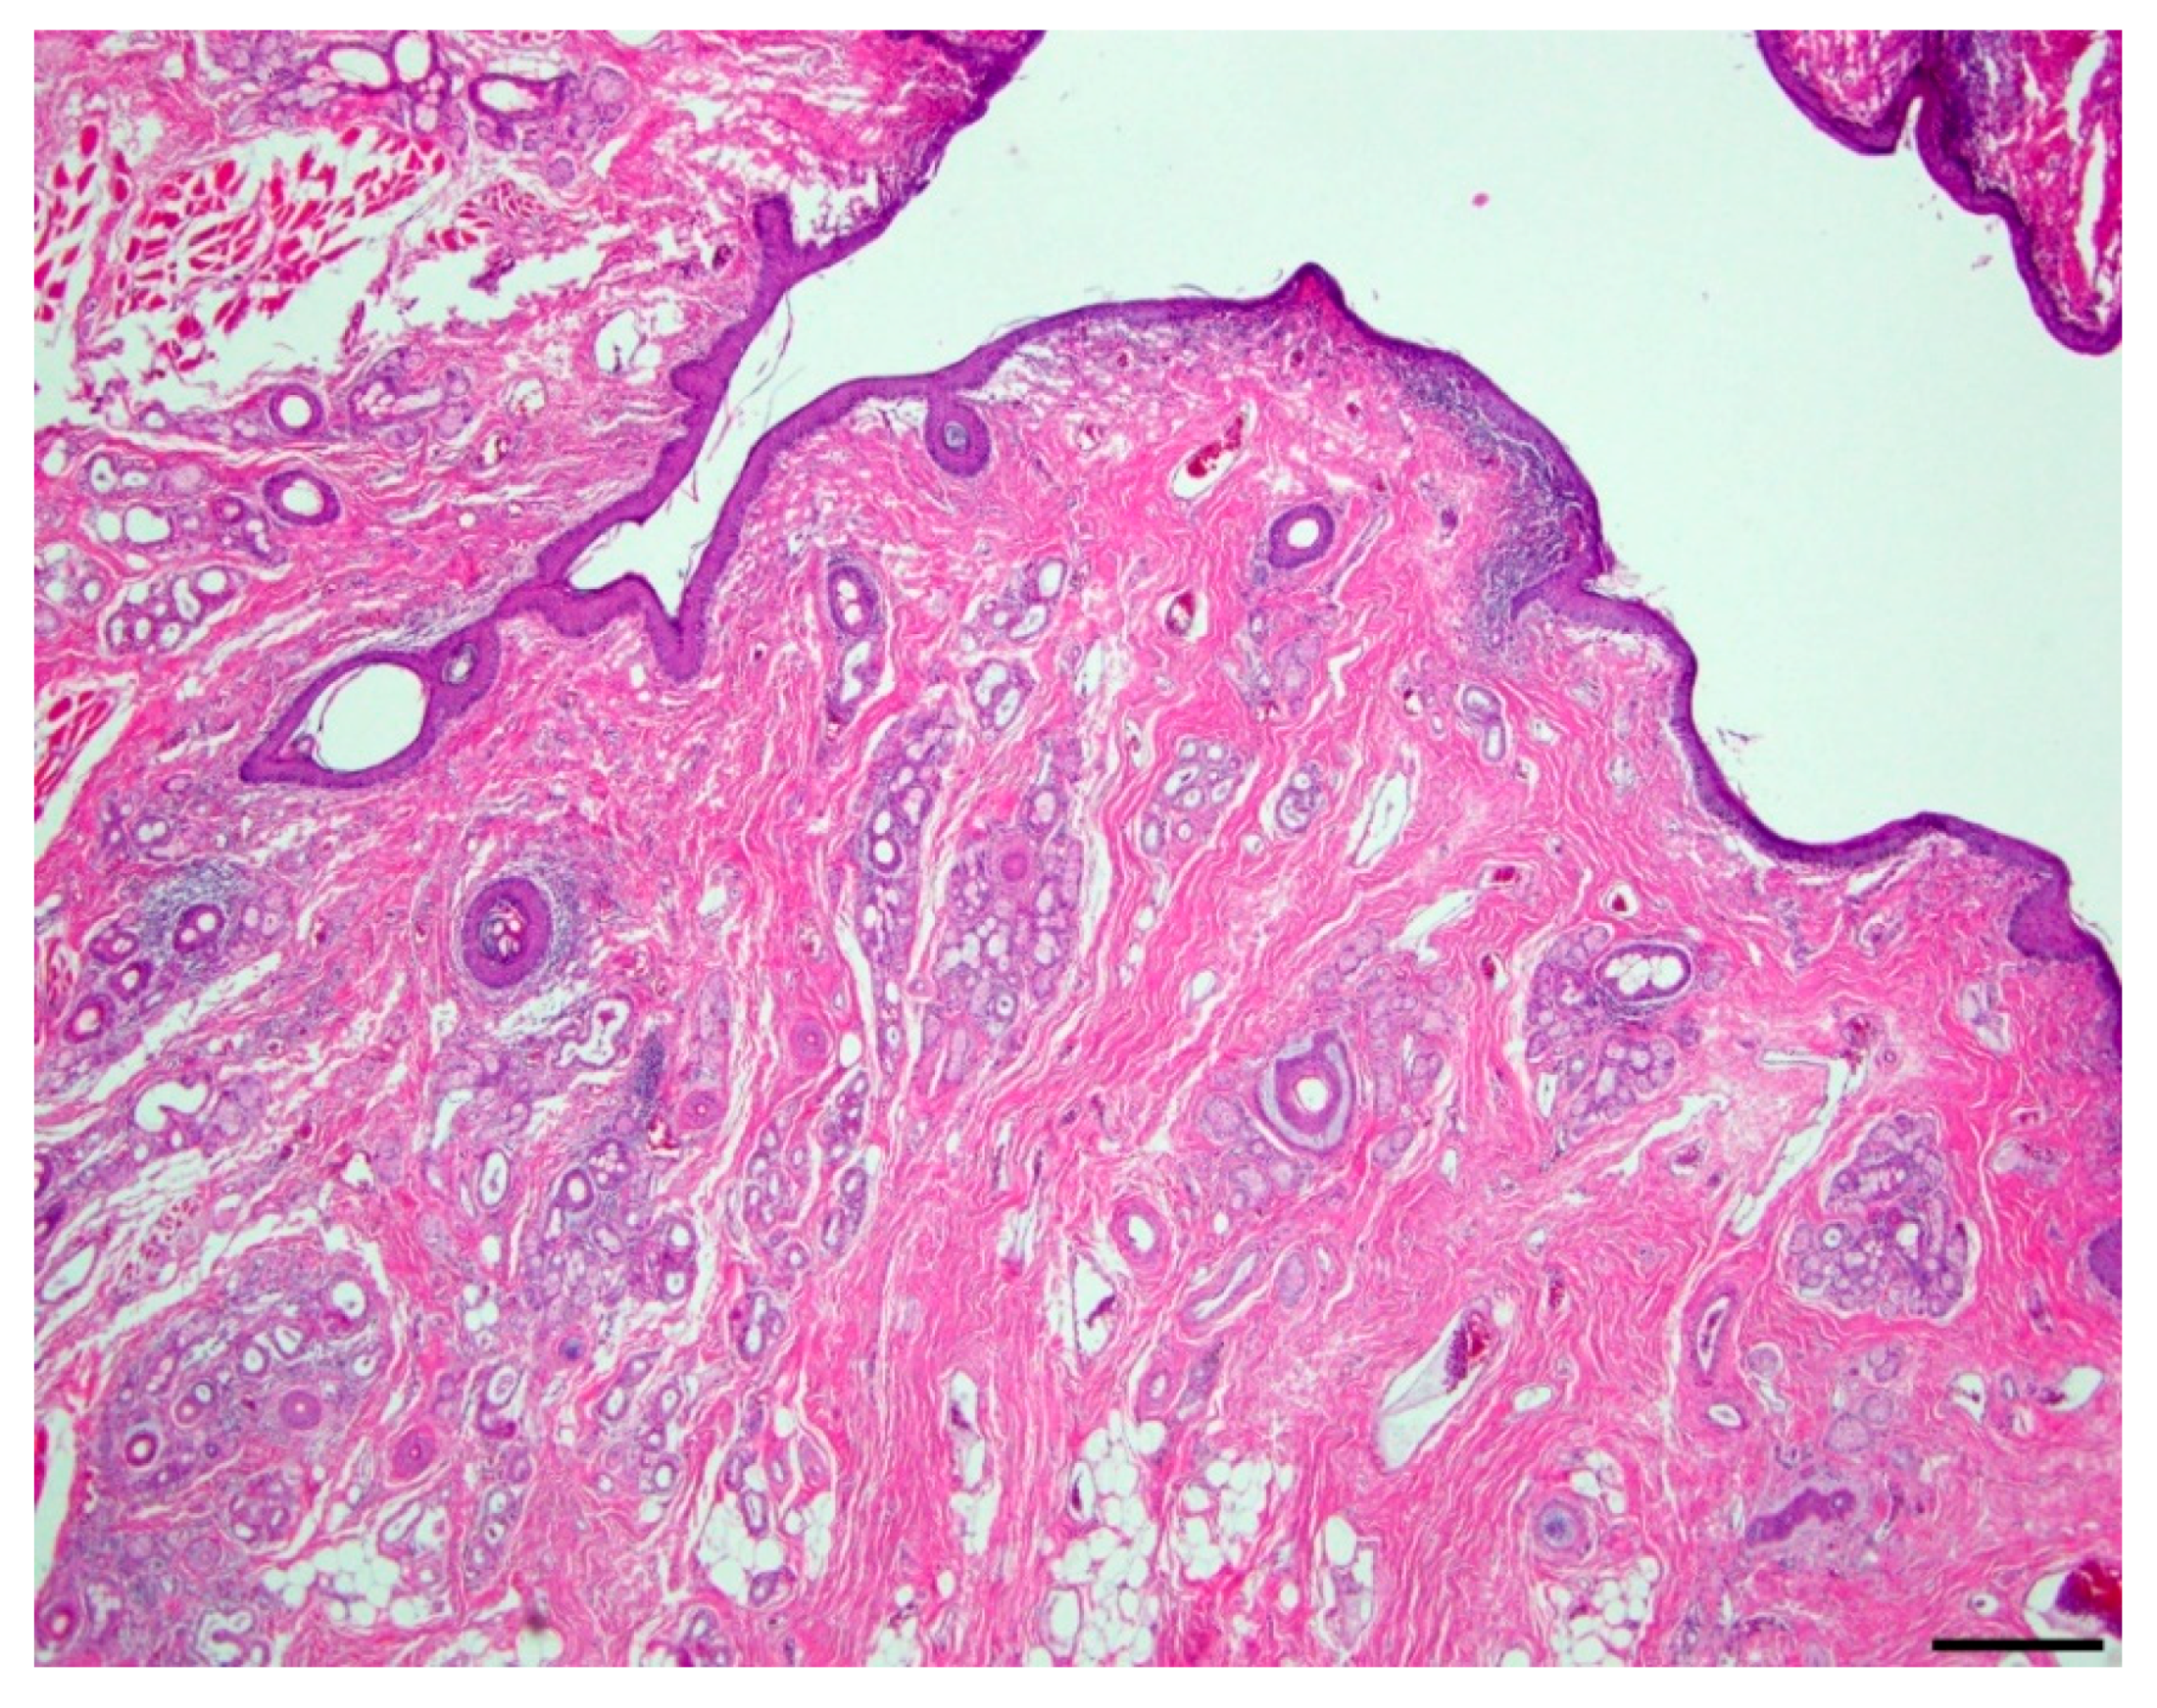

Microscopic evaluation of the mass revealed an unencapsulated, moderately cellular, well-demarcated expansile mass (Figure 1). The mass was centered on a lumen lined primarily by urothelium that multifocally transitioned to non-keratinizing, stratified-squamous epithelium (Figure 2). In portions of the mass lined by stratified squamous epithelium, the supporting stroma contained low numbers of hair follicles and associated sebaceous sweat glands with scattered apocrine glands (Figure 3). The lumen was surrounded by a dense collagenous stroma with few skeletal muscle bundles containing numerous, variably sized, dilated vascular channels with luminal erythrocytes (Figure 4). The vascular channels occasionally anastomosed and were lined by a single layer of endothelium. The sub-urothelial collagenous stroma was multifocally infiltrated and expanded by aggregates of lymphocytes and fewer plasma cells forming discrete aggregates (Figure 3).

Figure 2. Duplicated urethra, lumen (200x; hematoxylin and eosin). Multifocally, the urothelium lining the central lumen transitions to a non-keratinizing, stratified squamous epithelium. The supporting fibrovascular stroma contains low numbers of hair follicles with associated adnexa; bar = 100 µm.